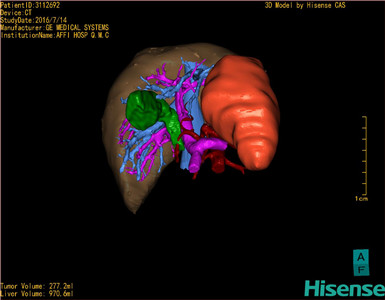

将0.625mm双源薄层CT资料的静脉期和动脉期Dicom格式文件导入海信CAS系统。

通过调节窗宽窗位调整CT序号,对肿瘤,肝实质,胆囊,下腔静脉,肿瘤,肝动脉、门静脉及肝静脉等进行三维重建;系统自动计算肿瘤体积和肝脏体积。

模拟手术操作,自动计算切除肿瘤体积。肝脏体积为970.6ml,肿瘤体积为277.2ml,肿瘤体积为肝脏体积的28.6%,通过比对60-70岁正常肝脏体积为1262.7±284.31 ml,通过术前模拟手术,精准判断切除后剩余肝脏体积能耐受,避免肝衰竭发生。

术前手术方案的规划。

术前三维重建:

重建图片